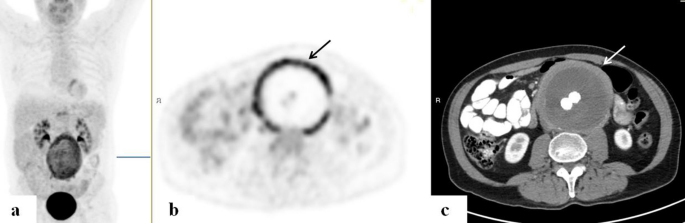

The presence of aortic aneurysm

Evidence of an abdominal aneurysm with enhanced uptake in that area, and extending into the bifurcation and along bilateral iliac arteries, was detected in a patient who was being monitored for a history of lung cancer. In another patient who was evaluated for FUO and very elevated inflammatory markers with a C-reactive protein (CRP) as high as 230 mg/dl (normal range 0–5), a mycotic aneurysm in the abdominal aorta was detected on the PET/CT. He was treated accordingly with surgical repair (Fig. 3).

FDG-PET/CT:Â maximum intensity projection (MIP) (a) a representative PET (b) and CT (c) axial slices. A 65-year-old man with mycotic aneurism of the abdominal aorta. PET demonstrates high intensity of increased uptake (arrows) along the markedly thickened wall of the dilated abdominal aorta following repair.